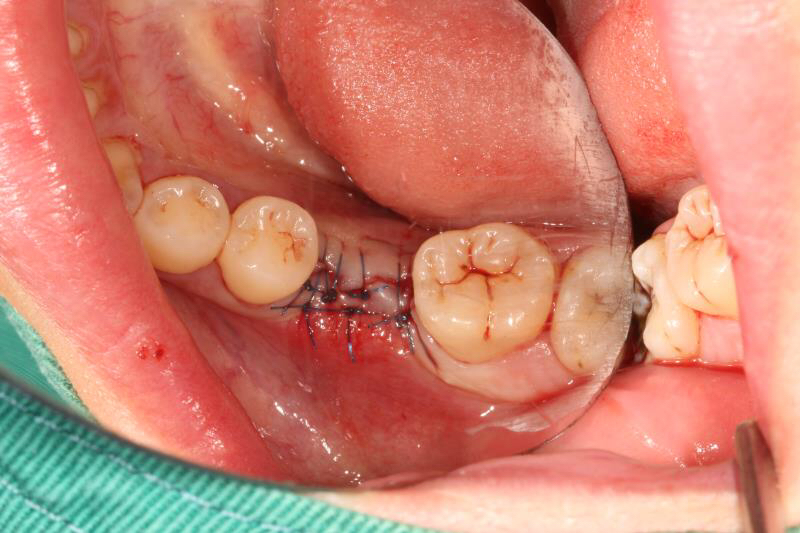

今天给大家介绍一个单颗后牙种植+局部正畸联合治疗病例。

患者年轻女性,后下6残根,因未及时修复,5、7号牙向6号牙倾斜,导致了修复空间不足。按照常规治疗方案,会损伤两侧的健康牙齿,得不偿失,所以我们为她采用了正畸+种植联合治疗方案。